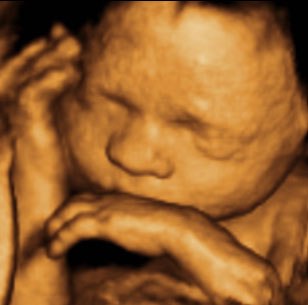

Kan da lige sætte et par billeder ind fra i mandags, hvor jeg var 27+5 uger henne, så du kan se kvaliteten

Vedhæftede fotos (klik for at se i fuld størrelse)